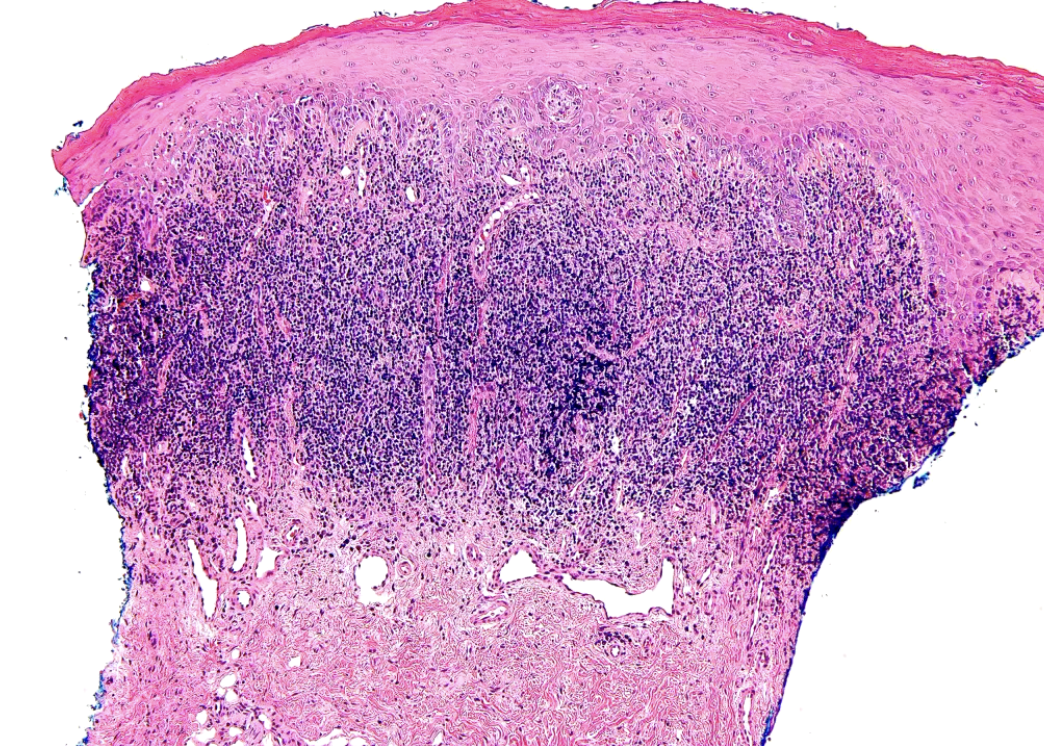

what are some histopathologic features of lichen planus?

• Orthokeratosis or parakeratosis

• Degeneration of basal cell layer

• Colloid bodies

• Saw tooth rete ridges

• Band-like infiltrate of lymphocytes